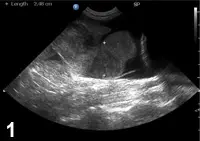

Hypovolemic or circulatory shock is the most common cause of shock seen in small animal practice. Hypovolemic shock results from a decreased intravascular volume, and causes commonly include hemorrhage, severe dehydration, and hypoproteinemia. Intraabdominal hemorrhage (Figure 1) may occur as a result of a ruptured splenic or hepatic mass, a coagulopathy, or trauma. Severe dehydration may be seen with prolonged fluid losses, as can be seen with vomiting and/or diarrhea.

An ultrasound image displays a transverse view of a canine abdomen, highlighting a fluid-filled structure near the liver. The measurement indicates a length of 2.48 cm, suggesting potential clinical significance for further evaluation.

Figure 1 Ultrasound image: peritoneal effusion and splenic mass